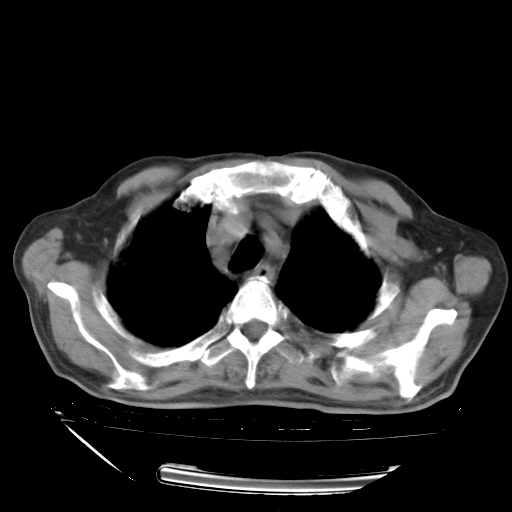

经过24天治疗,岳父的病情基本稳定。生活基本可以自理,可以下床活动。呼吸困难早已消失。体温基本正常。

主要治疗甲强龙80mg×14天,60mg×10天;同时抗结核(异烟肼+利福平+乙胺丁醇)。环磷酰胺0.1 tid 10天。

特别感谢胡教授、高管、桃子版主给出关键的治疗建议。桃版把所有肺部影像和全部临床资料请所在医院呼吸科、感染病科、结核科、临床免疫科专家会诊。临床免疫科专家制定了完整的治疗方案。